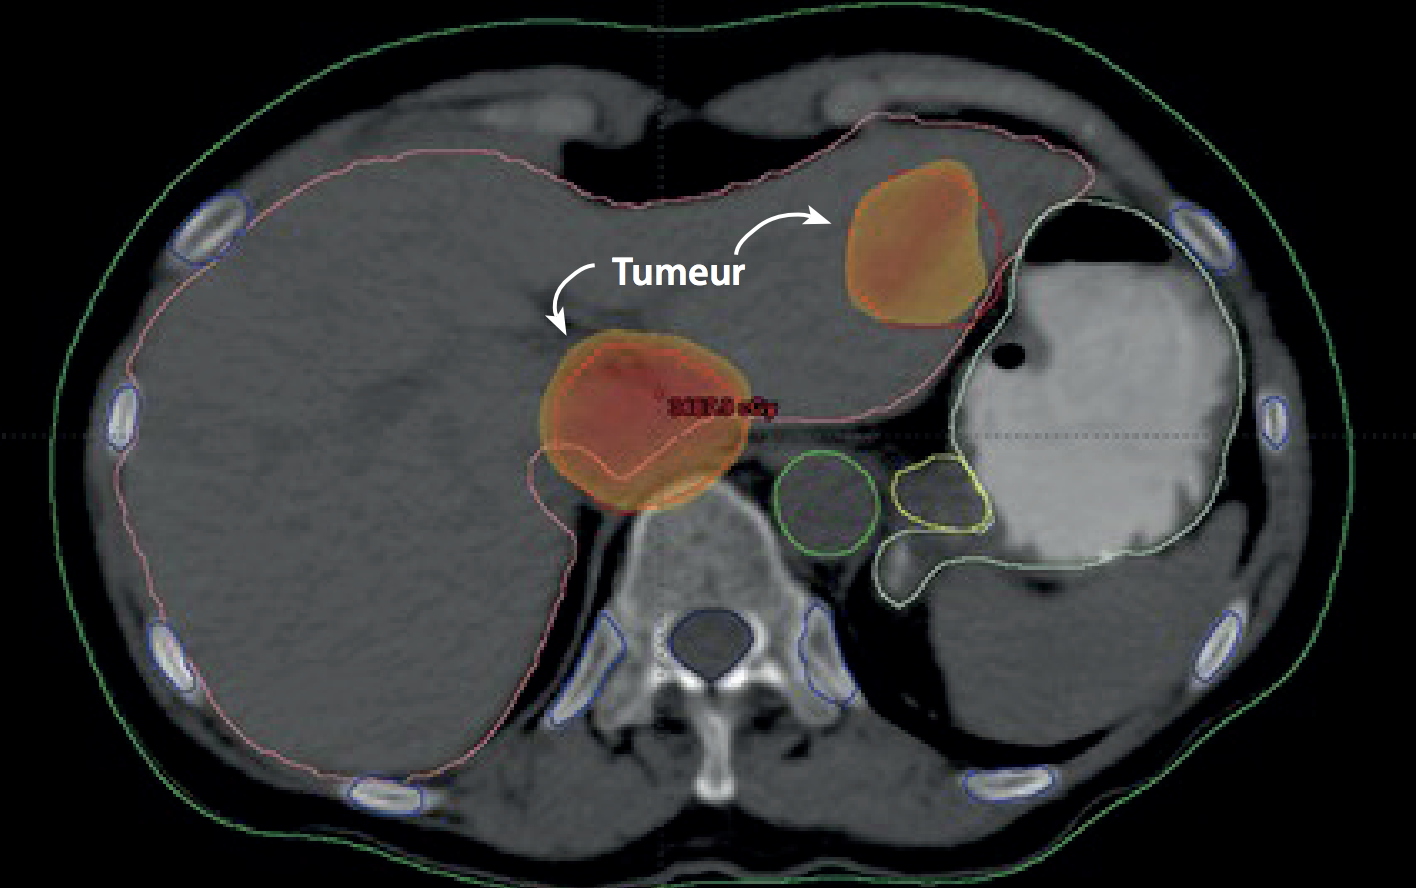

Un cas de cancer du foie qui sera traité par une forme avancée de radiothérapie, la radiothérapie stéréotaxique corps entier.(Photo : Institut national du cancer, égypte)

Tarek Shouman et l’équipe de l’Institut national du cancer utilisent maintenant la RSCE, en partie grace à l’aide de l’AIEA, pour lutter contre le cancer du poumon à un stade précoce, le cancer récurrent de la tête et du cou et un type de cancer du foie appelé carcinome hépatocellulaire (CHC), cancer le plus répandu chez les égyptiens males.

? Pour les cancers du foie comme le CHC, la RSCE a radicalement amélioré les possibilités de traitement par rayonnements ?, a expliqué Tarek Shouman. Le cancer du foie est aujourd’hui le troisième type de cancer qui entra?ne le plus de décès dans le monde. Pendant des années, il n’a pas pu être traité efficacement avec des rayonnements ; avec la radiothérapie classique, il est impossible d’administrer de manière s?re des doses de rayonnements suffisamment élevées pour traiter une tumeur au foie en raison des risques pour les tissus sains environnants. La RSCE permet de traiter même les toutes petites tumeurs du foie en administrant des doses de rayonnements plus élevées tout en préservant les tissus sains.